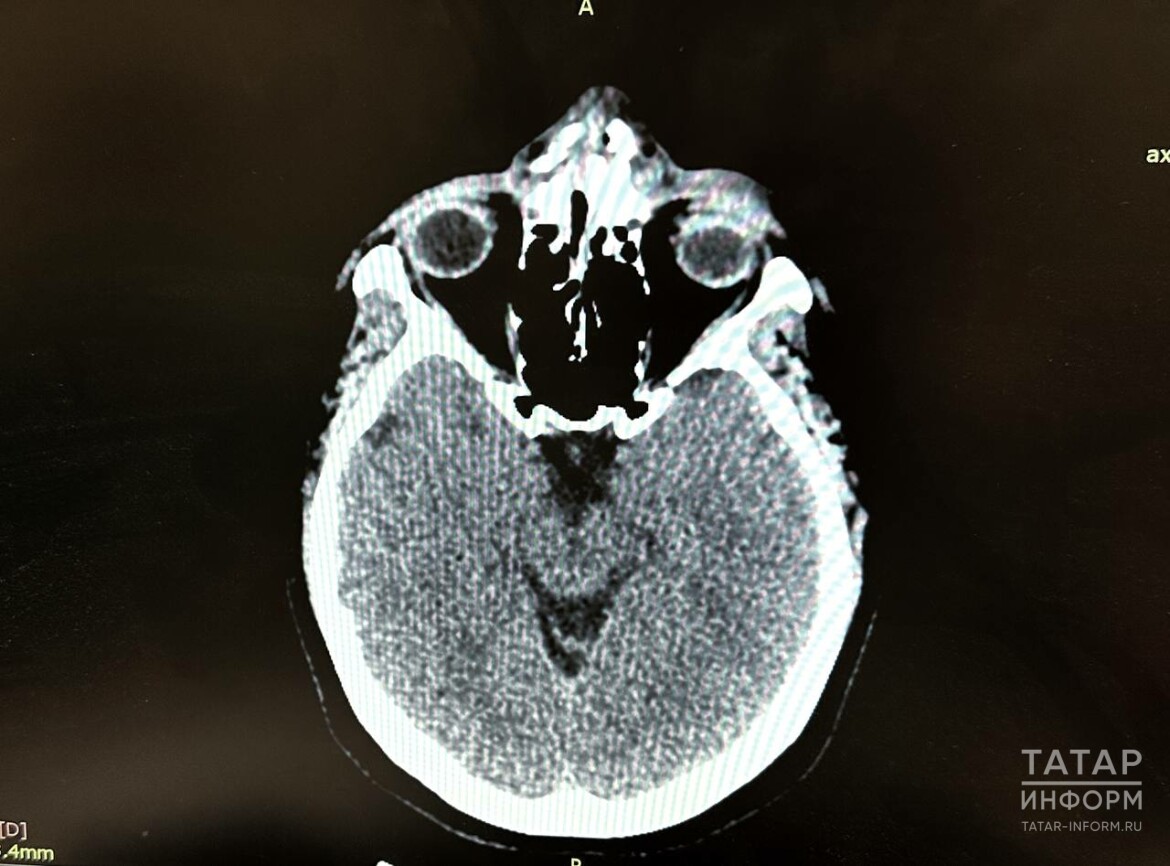

Оториноларингологи Республиканской клинической больницы Татарстана восстановили и сделали пластику носа 37-летней женщине, которая поскользнулась из-за гололеда. Об этом «Татар-информу» сообщили в пресс-службе РКБ Татарстана.

Женщина упала 24 ноября в Лениногорске, ударившись переносицей о ступеньку лестницы. Скорая помощь доставила женщину в ЦРБ, где ей диагностировали открытый перелом носа со смещением. Врачи наложили швы и перевели женщину в РКБ Татарстана.

Казанские врачи сделали репозицию костей носа и наложили внутрикожные швы, как при пластической операции.

Три недели женщине необходимо будет ходить с силиконовыми пластинами, после чего их уберут и нос окончательно восстановится.